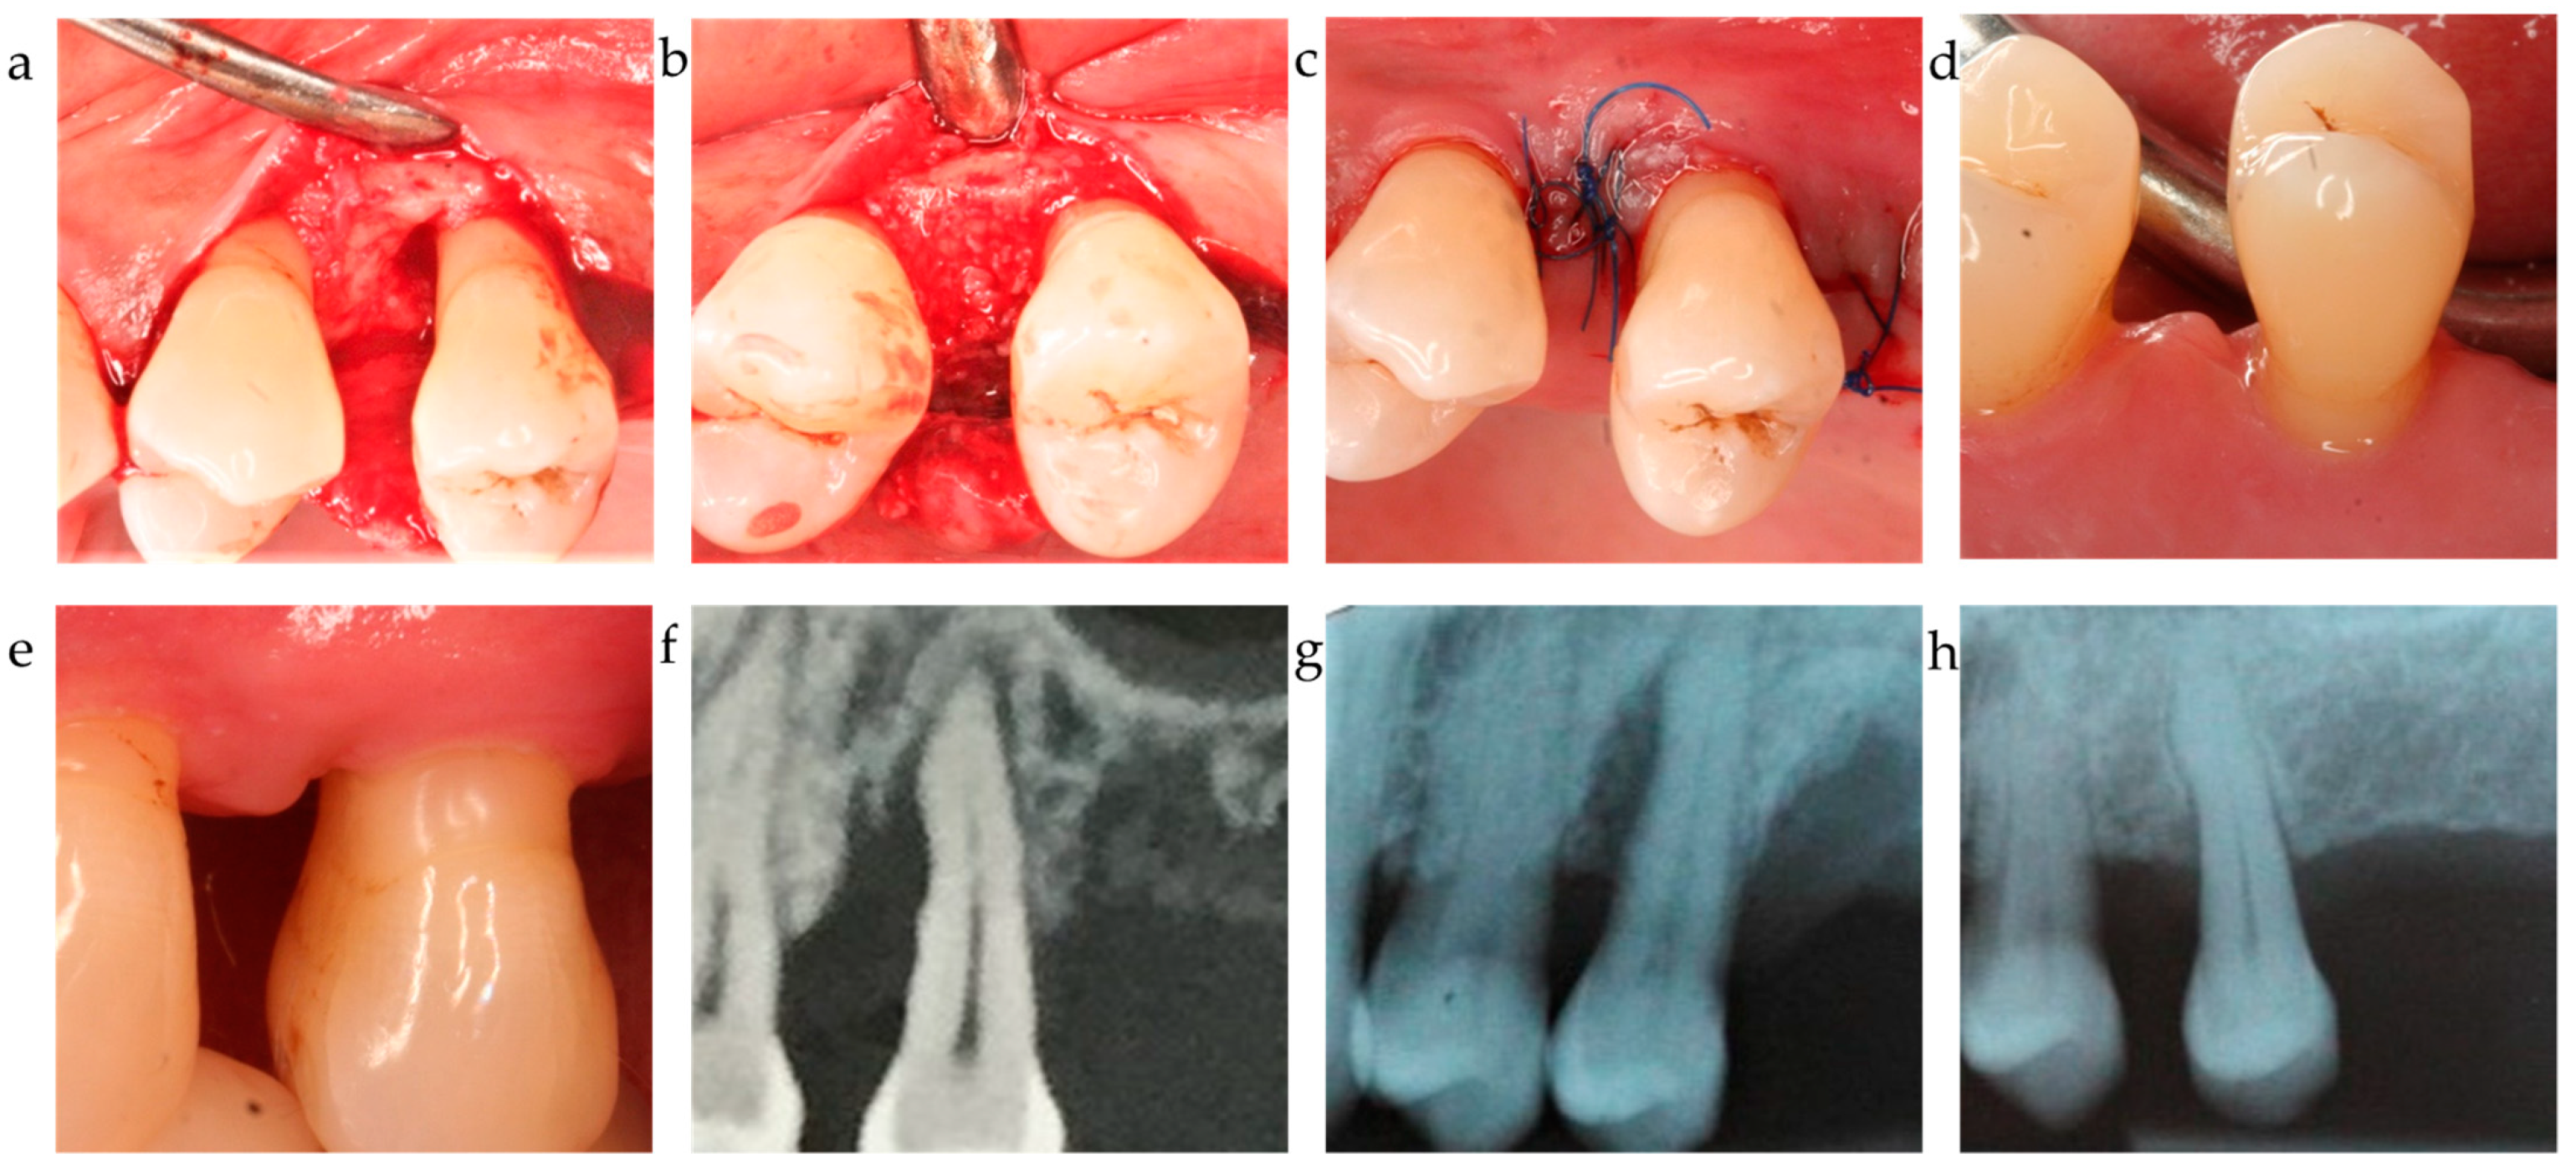

Figure 3.

Center 2 showcase: (a–c) defect extension, defect grafting at surgery, and suture; (d,e) clinical outcome at 12-month exam. (f–h) radiographically observed change in bone level around tooth 25 before surgery and 12 months post-op.

The ∆CAL comparison between centers favored center 2 vs. center 1 with a p = 0.006; the difference between C2 and C3 was statistically non-significant (p = 0.718). The radiographic bone fill was significantly greater in patients from centers 2 and 3 vs. center 1 (p = 0.003 and =0.014, respectively) (Table 4). The difference in radiographically documented defect fill between C2 and C3 was statistically non-significant (p = 1.0). As corroborated by the 12-month results, both the significant clinical attachment gain and radiographic alveolar bone improvement remained constantly unaltered during the observation period (Table 2, Figure 1, Figure 2 and Figure 3). The recession increased from baseline to the 12-month visit by 1.2–1.3 mm on average for center 1 and 3, while center 2 recorded a minimal recession increase of less than 0.5 mm.